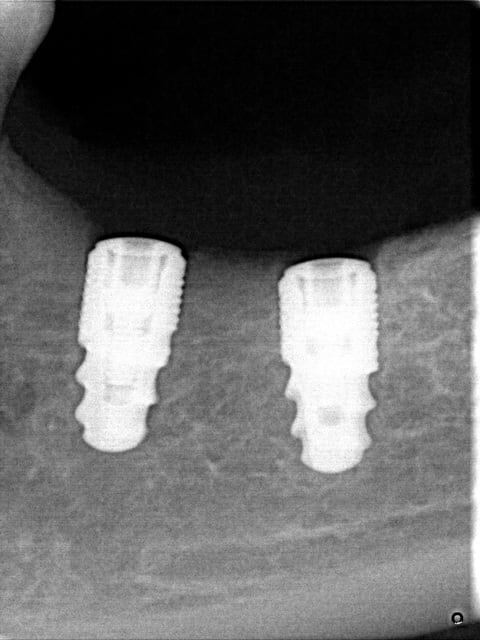

Merci pour vos réponses,au sujet de l'hypoesthésie ,je reçois ma patiente deux mois et demi après la pose des deux implants elle commence à sentir une sensibilité au niveau profond ,quel soulagement ,je prends une rvg et je découvre une réparation qui commence à se faire au niveau de la région qui a été lésée au moment de la pose !!!

je me permet de poster ses Rx qu'il m'a envoyé par émail